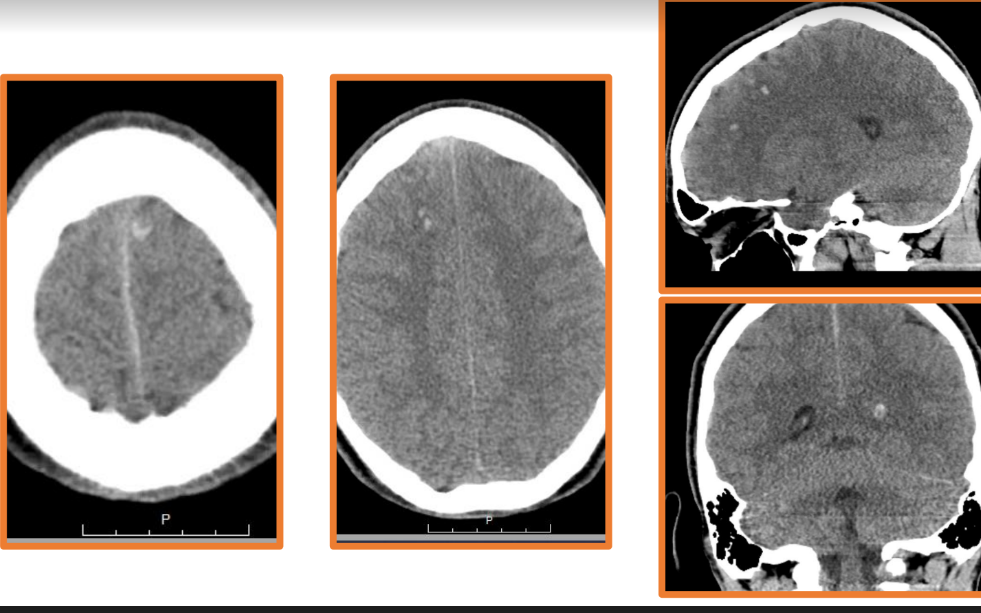

Here I have some CT and MRI images taken soon after my injury. The blurred parts of the MRI image towards the center show evidence of shearing. In addition, the bright white portions of the CT images represent accumulations of blood, known as hemorrhages. These also contributed to the extent of my injury. Had the emergency staff not implanted what is known as an intracranial pressure cup (ICP) to relieve the pressure from the excess fluid within my cranial cavity, my brain would have been displaced and squished down by the fluid, and the extent of my injury would have been much worse, potentially even fatal.